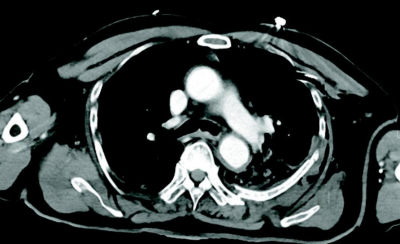

83 歳の男性。作業中に3 mの高さから転落し、背部痛と呼吸困難のため救急車で搬入された。胸腔ドレナージ後の胸部造影 CTを別に示す。

画像所見として認められるのはどれか。3つ選べ。

a. 気胸

b. 肺挫傷

c. 気管断裂

d. 縦隔気腫

e. 肋骨骨折